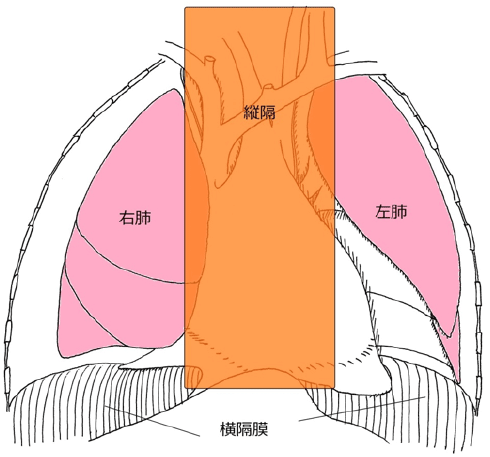

尿崩症 縦隔腫瘍 - Genspark, 縦隔腫瘍(じゅうかくしゅよう Mediastinal tumor) – 呼吸器疾患,

縦隔腫瘍(じゅうかくしゅよう Mediastinal tumor) – 呼吸器疾患, 尿崩症 縦隔腫瘍 - Genspark,